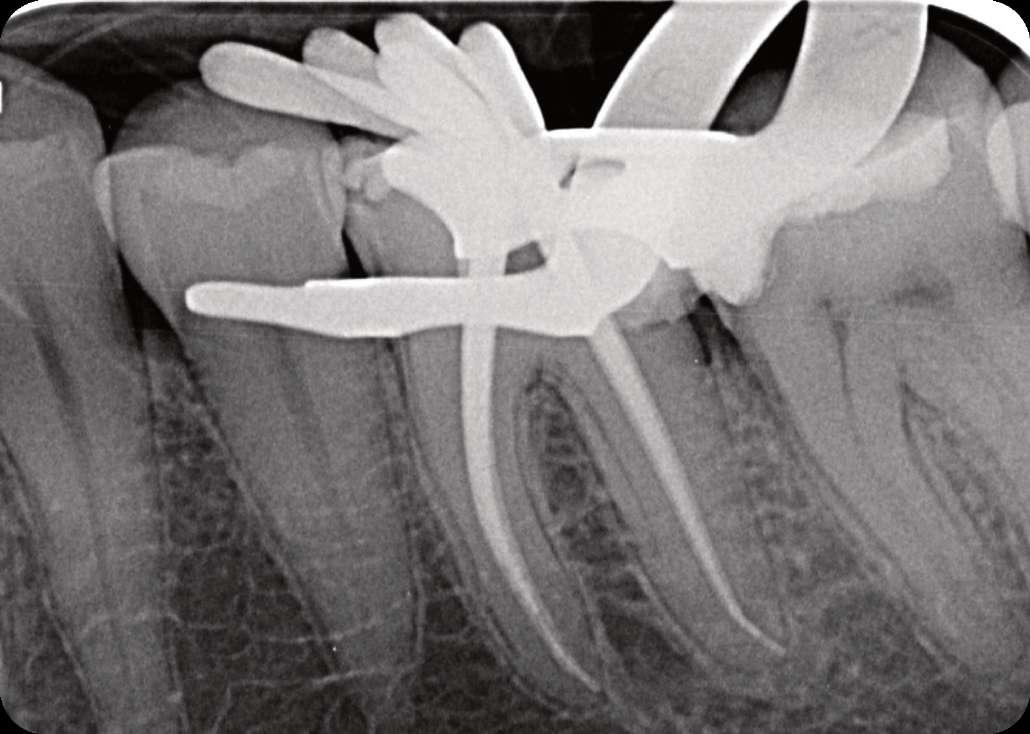

Wenn man sich dieses präoperative Röntgenbild ansieht, sind zwei Hinweise zu diesem endodontischen Fall zu erkennen (Abb. 1): Obliteration der Pulpakammer und enge Kanäle Ungewöhnliche Anatomie der distalen Wurzel

Mit hochtourigen Diamantbohrern wurde eine konventionelle Zugangskavität angelegt und die drei Öffnungen wurden mit Ultraschallspitzen lokalisiert. Die KFeile #08 wurde verwendet, um das endodontische System aller Wurzeln zu erkunden, wobei aber der Apex im distalen Kanal nicht erreicht werden konnte. Das Aufweiten und die Instrumentierung im mittleren Drittel erfolgten mit einer reziprok arbeitenden kleinen (gelben) EdgeOne-Feile (Edge Endo, Albuquerque, NM), die mit Einwärts-Auswärts-Bewegungen von 1-2 mm im Wechsel mit bürstenden Bewegungen zum koronalen Erweitern der Kanäle verwendet wurde. Es wurde eine regelmäßige und reichliche manuelle Spülung mit Lösungen von 5% Natriumhypochlorit durchgeführt. Nach der Aufbereitung des koronalen und mittleren Teils wurde die Arbeitslänge mit der K-Feile #10 bestimmt und das Aufbereitungsverfahren mit martensitischen X7-Instrumenten (Edge Endo, Albuquerque, NM) in den Größen 17 und 25, Konizität .04 abgeschlossen. Die Instrumente wurden mit reziproker Rotation im Uhrzeigersinn (150°-30°) verwendet, um die Torsions- und Biegebelastung zu verringern (Abb. 2).

FALLBERICHT: Abb.1 Abb.2

Die abschließende Spülung erfolgte zunächst eine Minute mit schallaktivierter EDTA-Lösung, gefolgt von einer Minute mit schallaktivierter NaOCl-Lösung. Das Wurzelkanalsystem wurde gespült, getrocknet und dann mit einer hydraulischen Single-Cone-Technik und einem biokeramischen Sealer (BUSA, BC Sealer) verschlossen. Zur Überprüfung der Behandlungsqualität wurden zwei periapikale Röntgenaufnahmen aus verschiedenen Winkeln angefertigt (Abb. 3-4).

Der Verdacht des Klinikers auf eine ungewöhnliche Anatomie der distalen Wurzel wurde durch das abgewinkelte Röntgenbild bestätigt, das eine abrupte versteckte Krümmung im apikalen Drittel des Kanals zeigte. Trotzdem ermöglichte der Crown-Down-Ansatz (zunächst Aufbereitung des koronalen und mittleren Teils, wodurch koronale Interferenzen reduziert werden) und die richtige Auswahl sehr flexibler und widerstandsfähiger

Abb.3 Abb.4